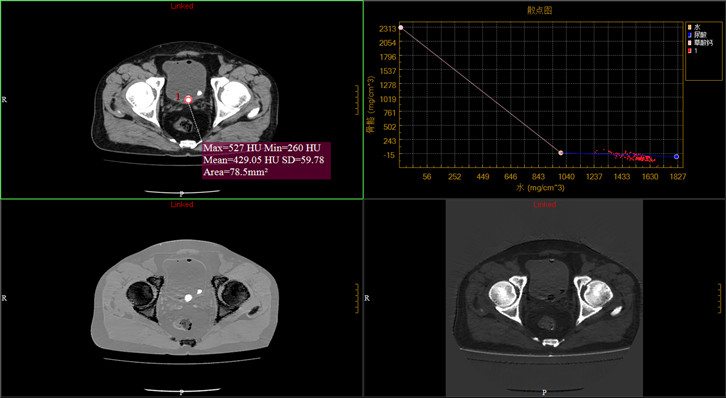

·Comprehensive 32 slices spectral imaging platform enables hospitals at all levels to enjoy the advanced functions of super high-end CT. Spectral imaging platform has rich clinical value in stone composition analysis, gout examination and tumor examination

Clinical Gallery